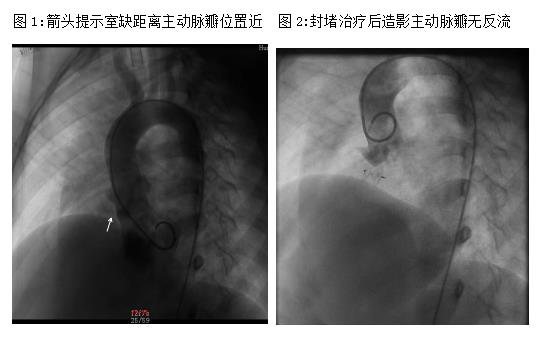

术中造影发现,患儿的室缺分流口2.1mm,距离主动脉瓣很近,应用常规室缺封堵器可能会造成明显的主动脉瓣反流。根据造影结果,医生跟家属再次沟通后,决定应用二代动脉导管未闭封堵器(ADO-Ⅱ)进行封堵。此封堵器质地更加柔软,延展性强,在封堵室缺的同时可最大限度的降低对主动脉瓣的损伤,术后心律失常的风险也会减少。短短1个多小时,患儿的室缺成功封堵,主动脉瓣没有任何影响,萌萌的室缺治愈。术后4天,萌萌顺利出院,且几乎无手术疤痕。